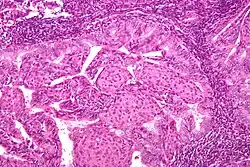

• Most are well-differentiated, with proliferation of endometrial glands without intervening stroma

• Endometrial hyperplasia is thought to be a precursor lesion developed with unopposed estrogen and genetic events

• Simple vs complex hyperplasia based on glandular architecture

• Cytologic atypia increases risk of progression to carcinoma (complex atypical hyperplasia risk ~30%)

• Cells show microsatellite instability, PTEN, and k-ras mutations

• Papillary serous (1-5%)

• Complex papillary architecture, similar to papillary serous CA of ovary

• Presence of psammoma bodies

• Marked nuclear atypia

• Believed to transform from endometrial surface epithelium